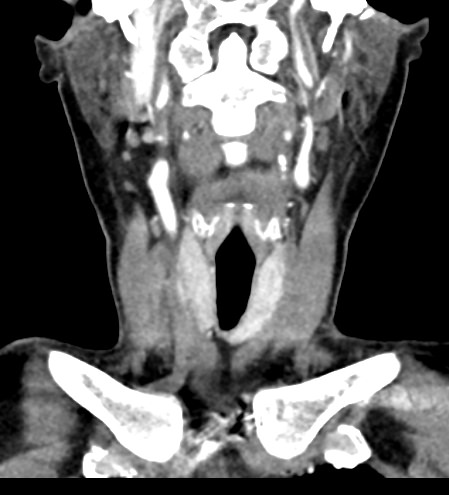

КТ щитовидной железы часто используется в диагностике доброкачественных и злокачественных опухолей железы, оценки распространенности процесса, поэтому для улучшения визуализации патологических очагов дополнительно применяется внутривенное болюсное контрастирование. Методика контрастирования позволяет увидеть на снимке опухоли минимальных размеров за счет того, что контраст избирательно накапливается в измененных тканях и обеспечивает яркое изображение патологического очага на фоне здоровых окружающих тканей.  Контрастирование дает возможность определить врачу границы опухоли, ее размеры, степень васкуляризации, точное расположение, особенно это важно при нетипичной (загрудинной) локализации органа.

В наших центрах обследование щитовидной железы выполняется на современных мультиспиральных томографах TOSHIBA AQUILION, оснащенных увеличенным количеством сверхчувствительных детекторов, позволяющих производить множество срезов с минимальной толщиной от 0,5 мм. Инновационные возможности аппаратов обеспечивают получение множества послойных снимков высокого качества и построение на их основе трехмерной модели органа. Кроме того, аппаратура позволяет за счет сокращения времени сканирования минимизировать лучевую нагрузку на пациента.

Мультиспиральная компьютерная томография позволяет точно определить размеры и расположение щитовидной железы, выявить опухолевые образования, оценить их структуру, степень кровоснабжения, взаимодействие с окружающими тканями.